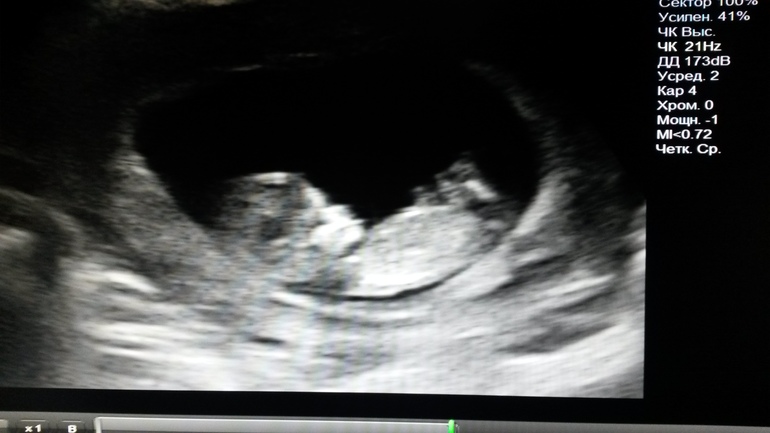

1ый скрининг или 57 мм счастья)

Кстати! Викуля на первом скрине у меня тоже была 57 мм))) Человечек мой любимый